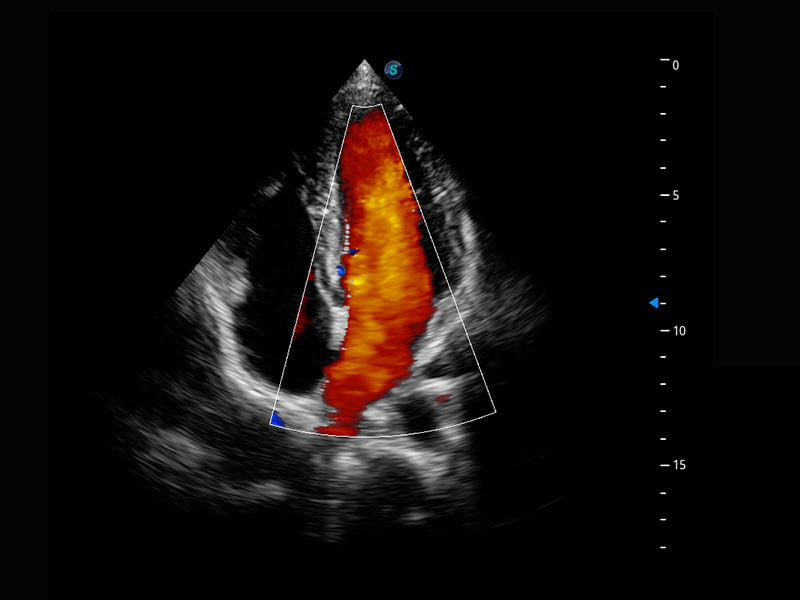

四腔心血流